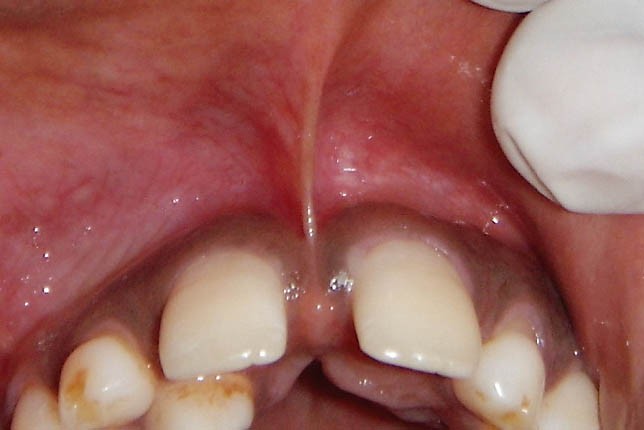

Frenulum (yüyən), diş əti toxuması (gingiva) ilə dil, dodaq və yanaq arasında yerləşən, toxumaları bir-birnə bağlayaraq hərəkətlərini sərhədləndirən yumuşaq selikli qişa toxumasıdır. Frenulum normal ölçülərdən böyük və qalın olduqda və ya diş əti kənarına yaxın yerləşdikdə bəzi narahatlıqlara və məhdudiyyətlətə səbəb ola bilir. Diş əti çəkilməsi, estetik məhdudiyyət, diastema, çıxan protez istifadə edən şəxslərdə protez fiksasiyasının məhdudlaşması və s. durumlar bununla bağlı ola bilir.